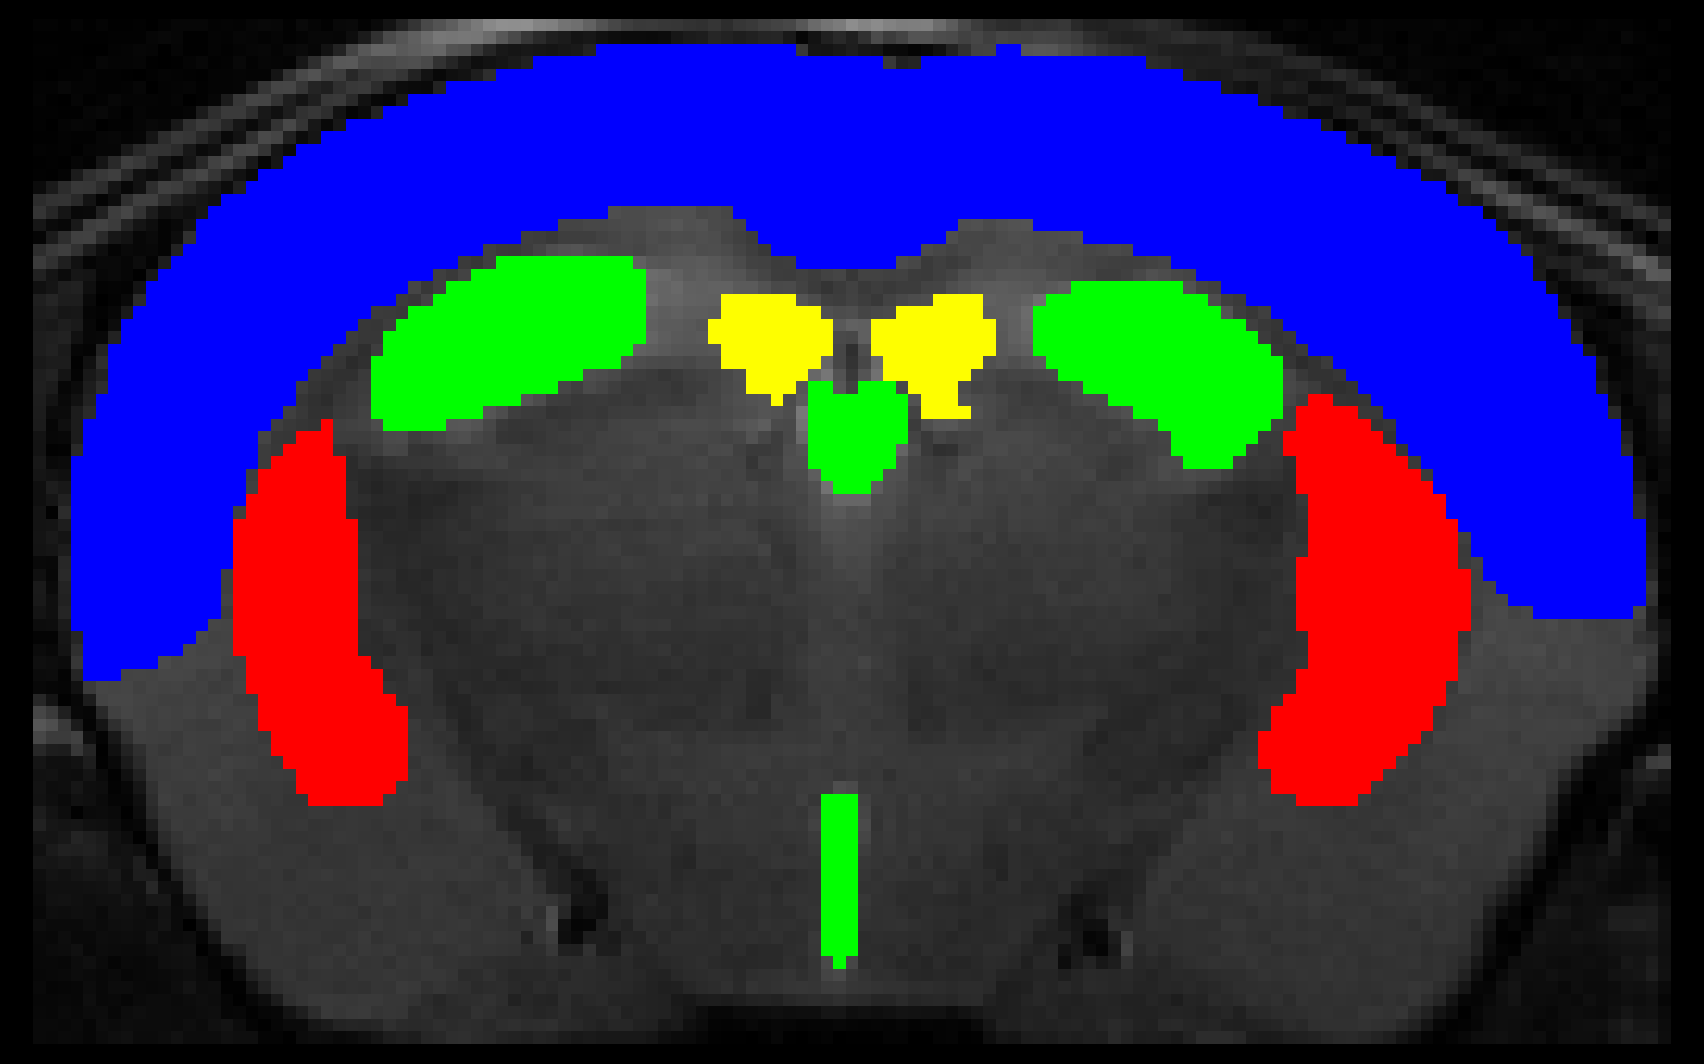

Multi-task U-Net for the simultaneous segmentation and skull-stripping of mouse brain MRI

This convolutional neural network is designed to perform skull-stripping and region segmentation on mouse brain MRI. A jupyter notebook going over the deails of this project and the training procedure is available here.

This network is trained on coronal T2 mouse brain MRI delineated with a bounding box, and so for the network to function correctly MRI volumes need to be cropped to a bounding box around the brain. To automate this task we include a lightweight auxiliary network. You can exclude this step by using the "--boundingbox False" option.